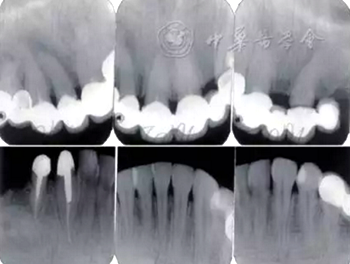

口腔衛(wèi)生狀況一般,菌斑指數(shù)0~2,鄰面少量軟垢;牙齦齦緣鮮紅、水腫、質(zhì)軟,出血指數(shù)2~3,余牙牙齦輕度水腫,出血指數(shù)0~2;全口探診深度2~3 mm,個(gè)別位點(diǎn)探診深度達(dá)4~5 mm,鄰面可探及附著喪失;未查及牙齒松動(dòng)及根分叉病變;烤瓷固定橋修復(fù),冠邊緣密合度欠佳,位于齦下1~2 mm;、唇側(cè)崩瓷,邊緣暴露;上前牙牙齦線不協(xié)調(diào);缺失,右下后牙可摘局部義齒修復(fù),固定橋修復(fù);近中面銀汞充填,近中懸突及繼發(fā)齲;上前牙覆蓋下前牙牙冠的1/2~2/3(圖1)。

圖1 患者初診時(shí)臨床照片 A:正面微笑像;B:正面口內(nèi)像